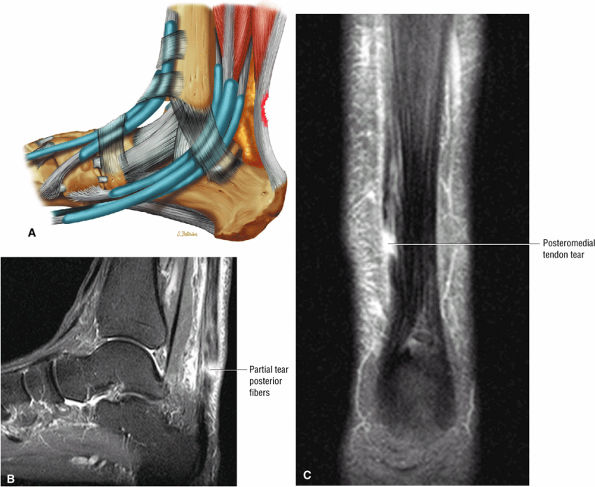

FIGURE 5.121 ● (A) Posterior surface partial tear of the Achilles tendon proximal to the os calcis. Lateral color lateral illustration. Sagittal (B) and coronal (C) FS PD FSE images of a partial tear of the Achilles tendon. The coronal plane image (C) is useful in demonstrating medial tendon fiber disruption.

FIGURE 5.122 ● Attenuated anterior-to-posterior tendon thickness in an extensive partial Achilles tendon tear without a tendinous gap. (A) Sagittal T1-weighted image. (B) Axial FS PD FSE image.